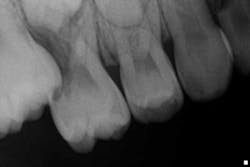

Case report A healthy 7-year-old female presents for a routine examination and cleaning (she had not been seen for two years). Crowding was noted primarily in the mandibular arch; the maxilla had a high palate. A significant amount of plaque/debris was noted in the upper right area between partially erupted No. 3 and tooth A. A bitewing radiograph on the right side barely revealed an ectopic eruption of tooth No. 3. (Fig. 1)Fig. 1Periapical and panoramic radiographs were taken and exposed a 50% resorption of the distal root and pulp chamber of tooth A. (Figs. 2 and 3)

Fig. 3Tooth A was not mobile nor was there any pain or discomfort to the area (despite the moderate amounts of plaque and debris). A referral was made to an orthodontist.